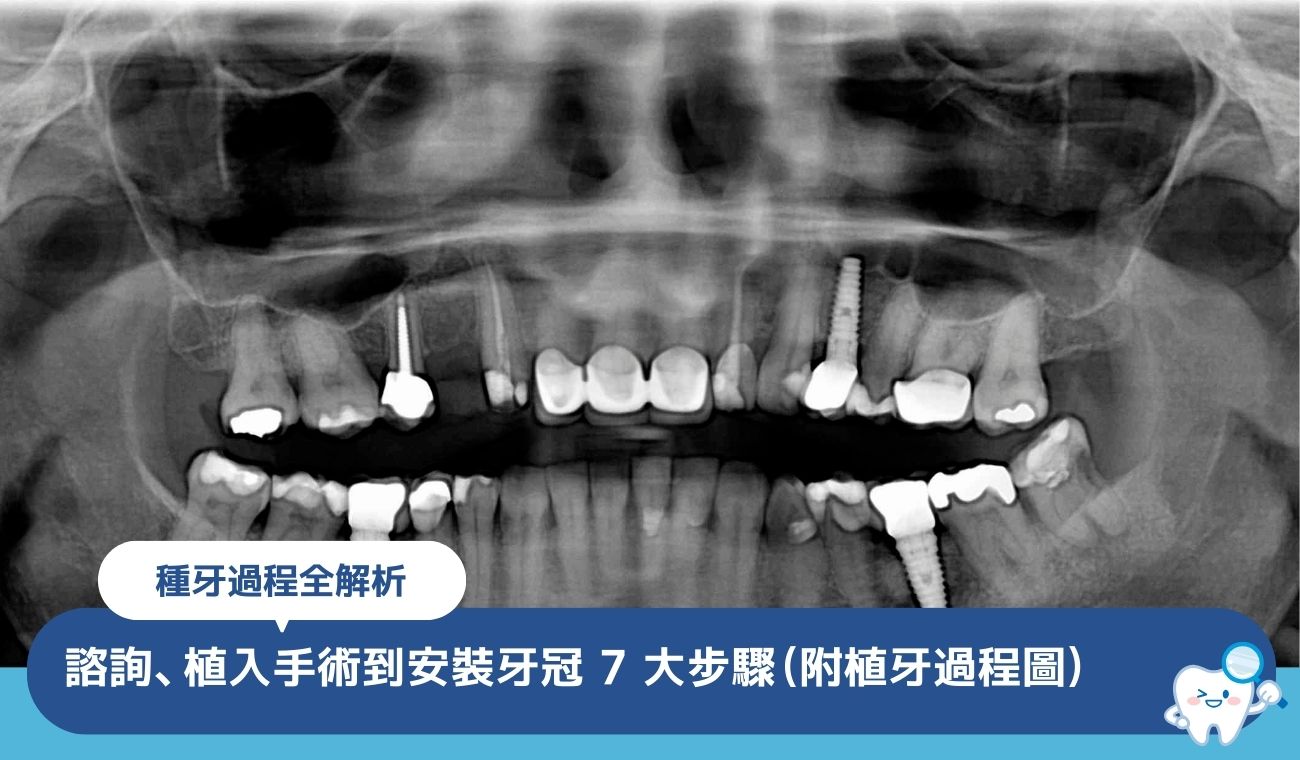

傳統的 X 光片(OPG)只能看到平面影像,無法呈現前後深度。

對於高風險的個案,通常會建議加做 3D 電腦掃描(CBCT)。 這樣醫生就能看到神經線是在牙根的前面、後面還是由中間穿過,進一步規劃出安全的手術切入角度。